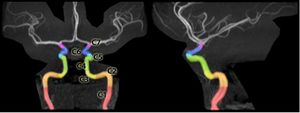

الشريان السباتي الغائر، يقع على الجانب الداخلي من العنق على الجانب المقابل للشريان السباتي الظاهر.[1] في التشريح البشري، تتفرع الشرايين السباتية الغائرة من الشرايين السباتية الأصلية حيث تتشعب هذه الشرايين السباتية الغائرة والظاهرية عند مستوى الفقرة العنقية 3 أو 4؛ يوصل الشريان السباتي الغائر الدم للمخ بما في ذلك العينين،[2] بينما يوصل الشريان السباتي الظاهري الدم لمناطق أخرى في الرأس، مثل الوجه، فروة الرأس، الجمجمة، والسحايا.

C1: القسم القحفي

C2: القسم الصخري

C3: القسم الثُقبي

C4: القسم الكهفي

C5: القسم السريري

C6: القسم الشرايين العينية

C7: قسم الشرايين الموصلة